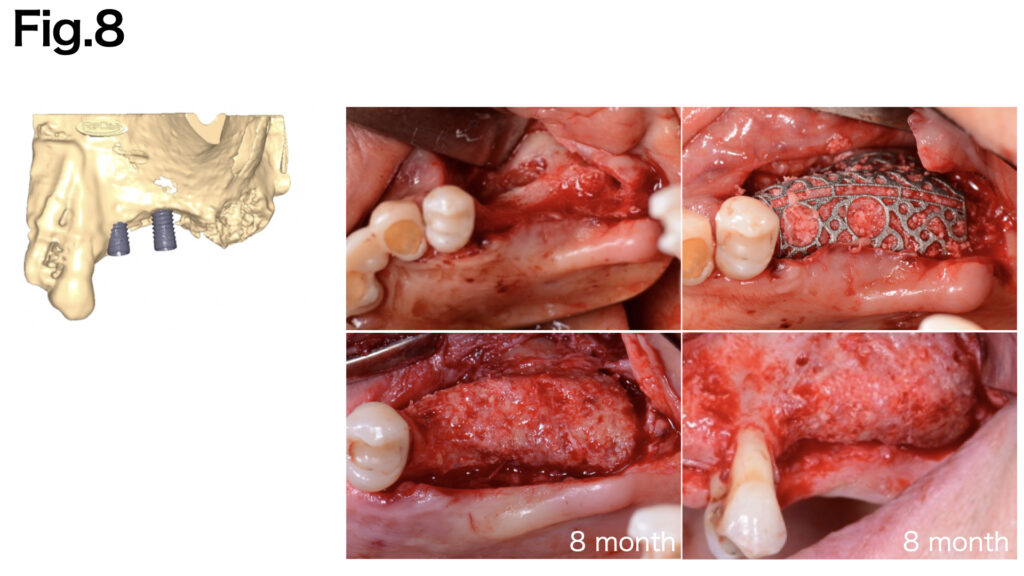

Titanium Mesh

Structure and properties

- Features high-form stability through a pure titanium mesh structure

Features and functions

- Promotes blood flow maintenance

- Adaptable to complex three-dimensional bone defects

- Enables secure fixation when combined with titanium screws

- Can be customized using CAD-CAM technology to match the specific defect

Suitable applications

- Particularly indicated for Type V (vertical bone defects)

- Achieves predictable outcomes in extensive vertical bone augmentation cases

- Ideal for complex three-dimensional defects

Precautions

- Requires collagen membrane coverage to prevent mesh exposure and soft tissue invasion into the mesh

- Necessitates secondary surgery for removal

- High risk of infection upon exposure

- Risk of tissue damage during removal due to soft tissue integration into mesh structure

CASE 5 (Type Ⅴ)

The vertical bone defect was identified. Fixation pins were applied to achieve secure fixation of the titanium mesh (Yxoss CBR® (ReOSS)). After six months of healing, adequate bone regeneration was achieved.